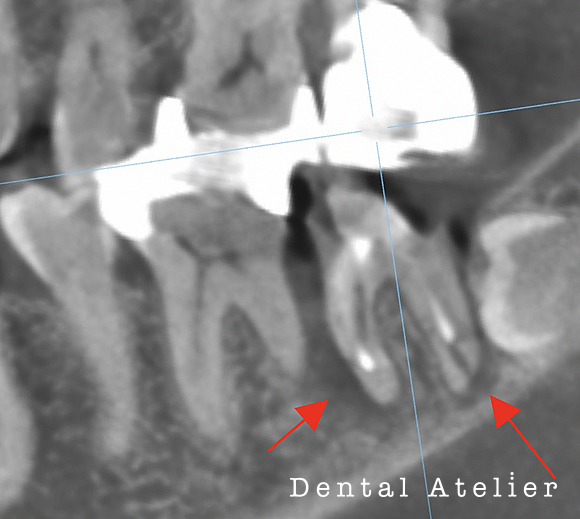

根の先の膿を診断され、治療を「抜歯」と言われた患者さんが来院されました。

当院にて、マイクロスコープ下で自費の精密根管治療を行いました。

MTAセメントにて根管充填を行い、5か月後のCT写真です。

初診時

5か月後

初診時、矢印の先にあった黒い影(膿の袋)が5か月後には無くなり、溶けた骨が再生してきています。

完全に骨化するには半年以上かかる見込みです。